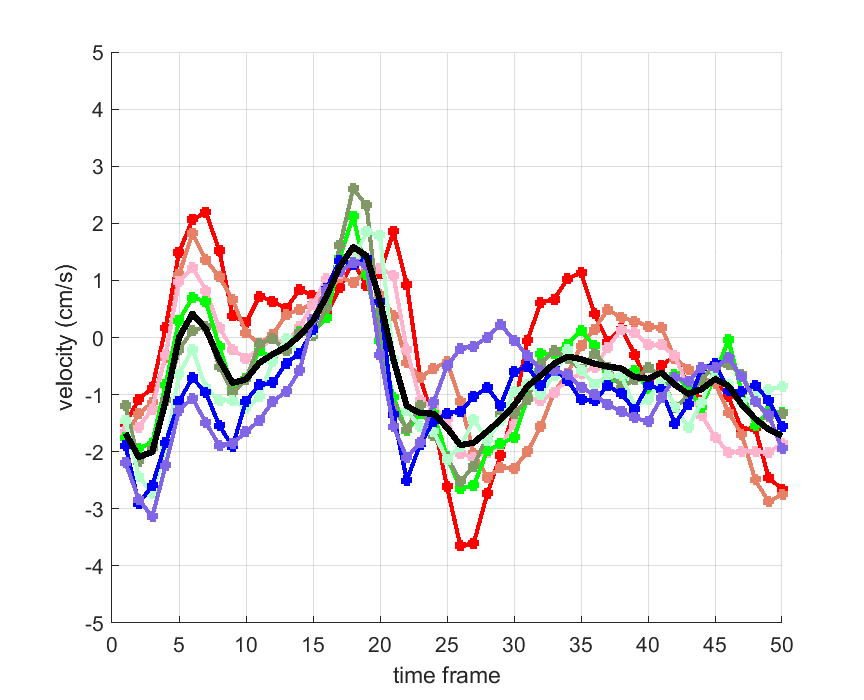

Time courses of the estimated translational component per subject, frame, slice and volume along the 3 velocity directions x, y and z are presented in Fig.6 - Fig.8.